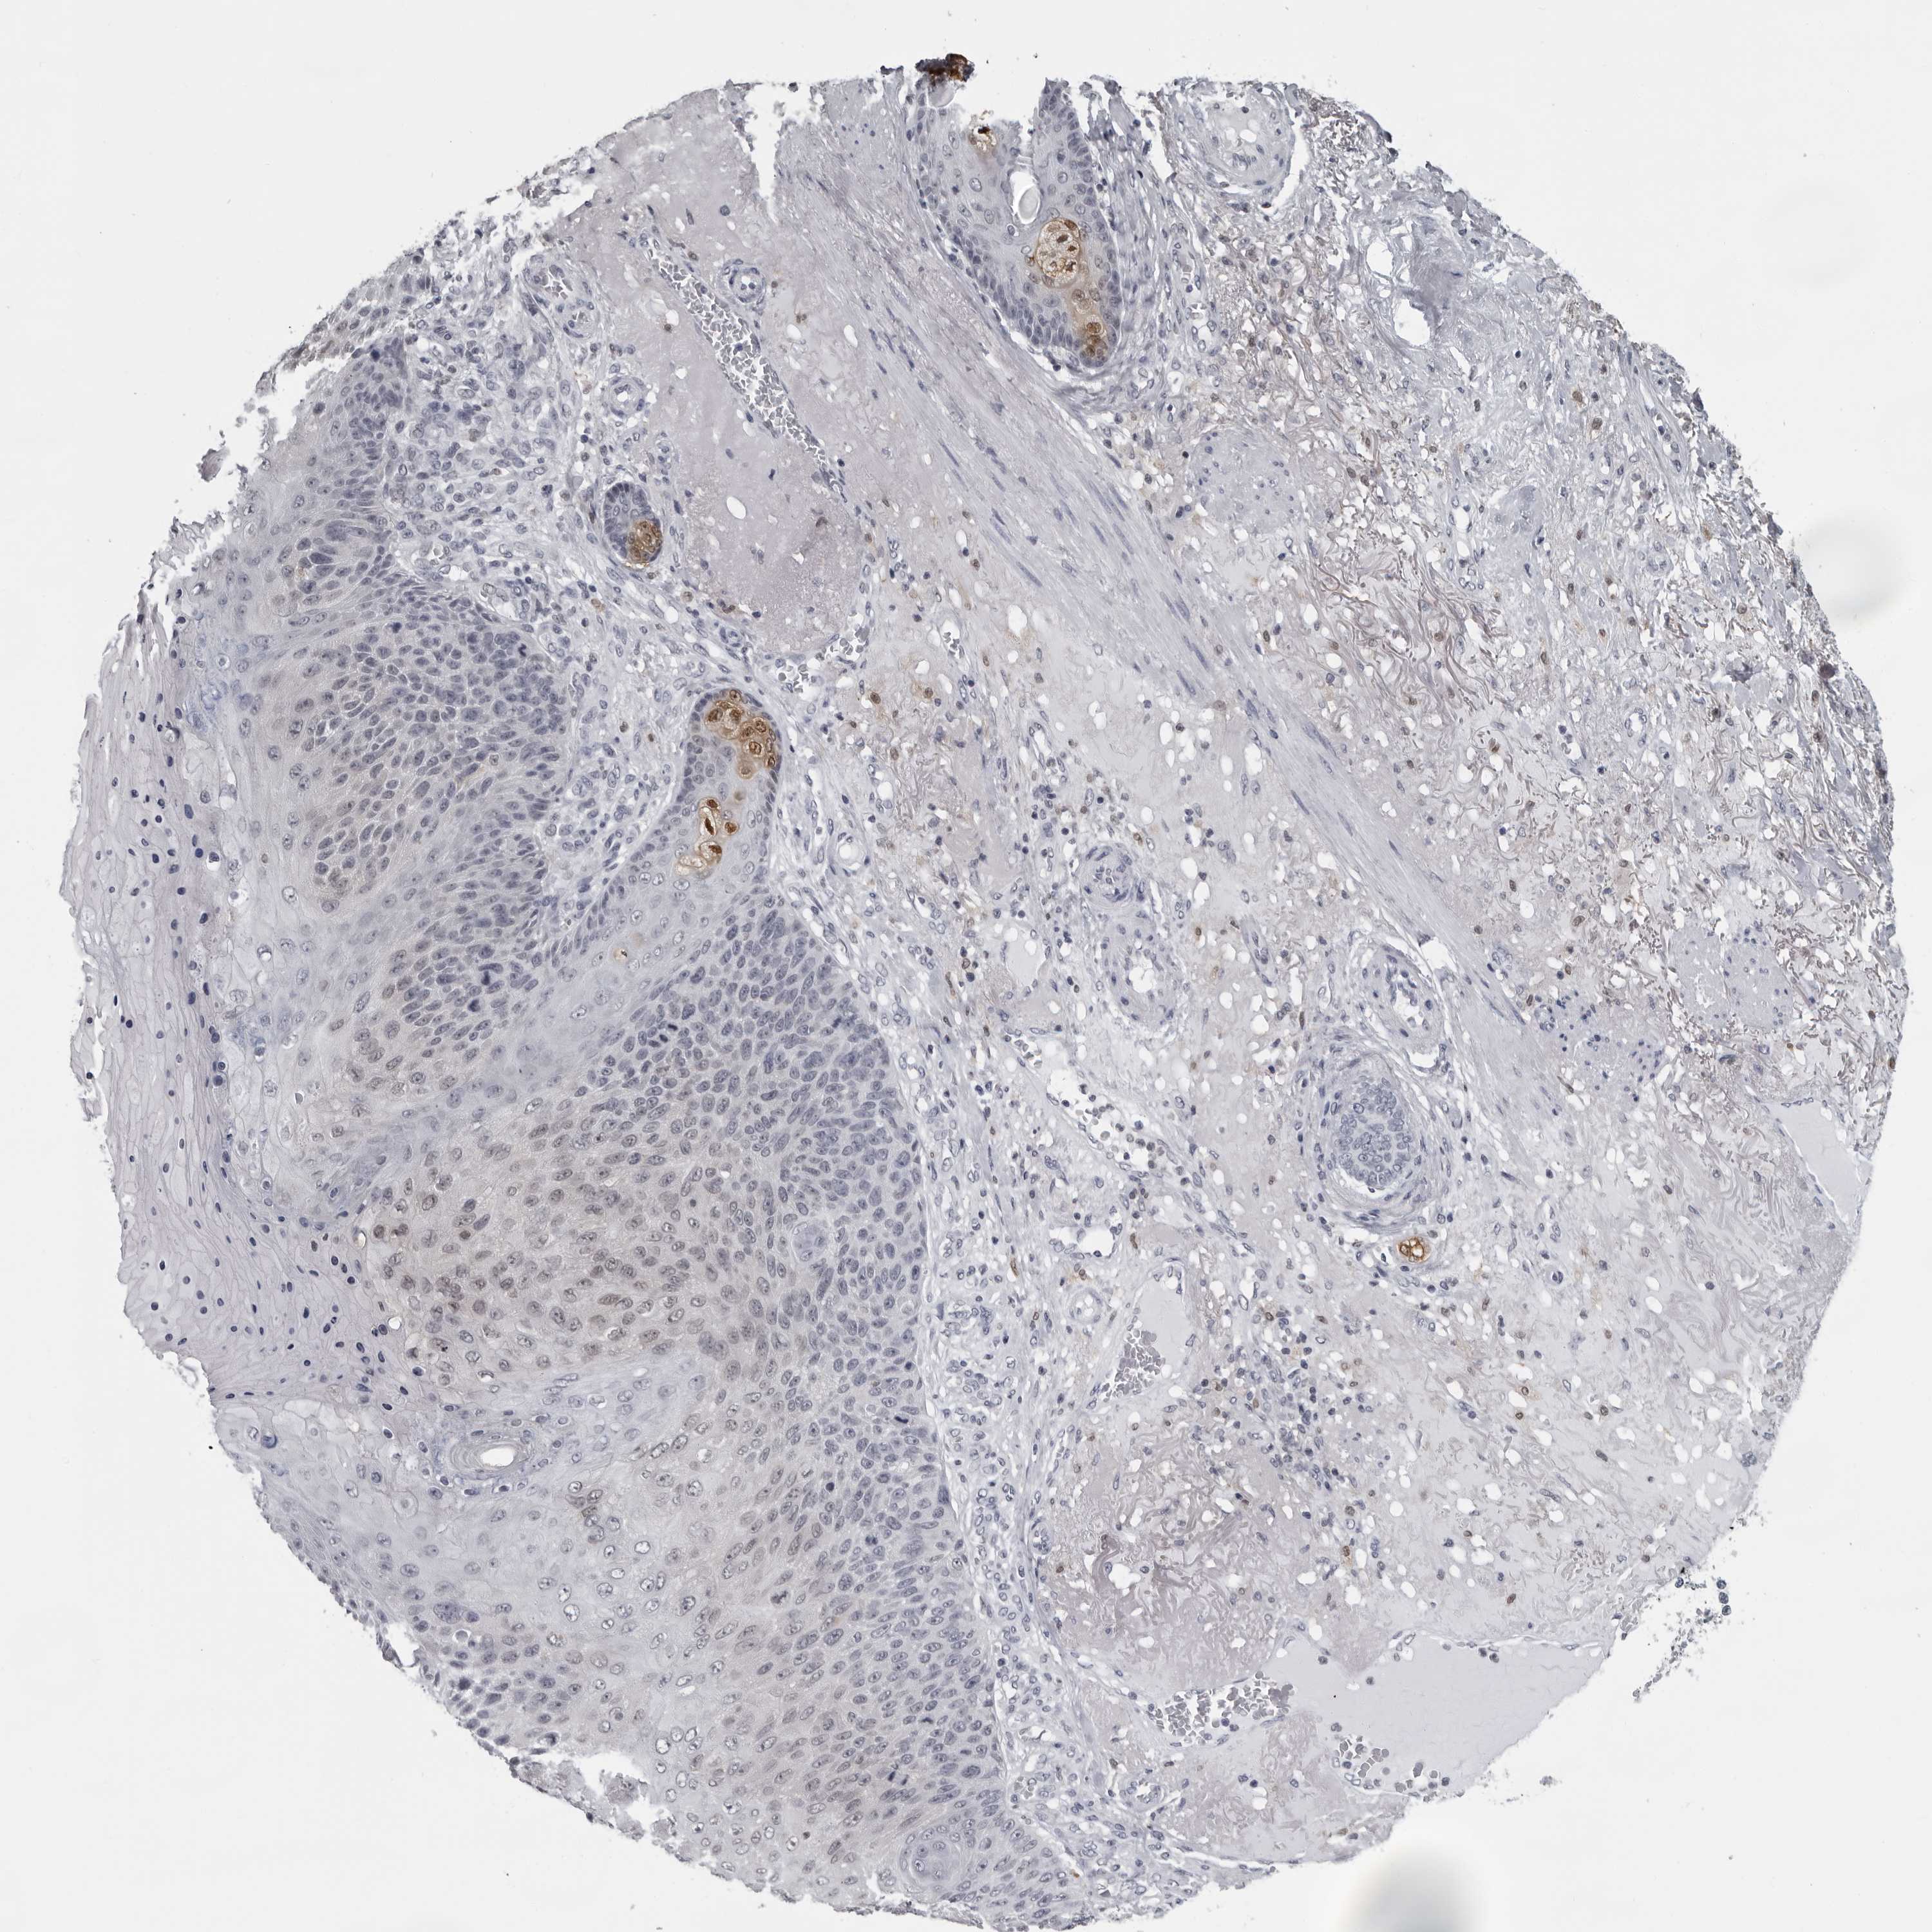

SKIN CANCER - Protein expressioni

A mouse-over function shows sample information and annotation data. Click on an image to view it in a full screen mode. Samples can be filtered based on level of antibody staining by selecting one or several of the following categories: high, medium, low and not detected. The assay and annotation is described here.

Each image is clickable and will lead to virtual microscopy that enables deeper exploration of all samples and also displays staining intensity scores, fraction scores and subcellular localization as well as patient and tissue information for each sample.

Antibody HPA028184

Staining

Squamous cell carcinoma, NOS